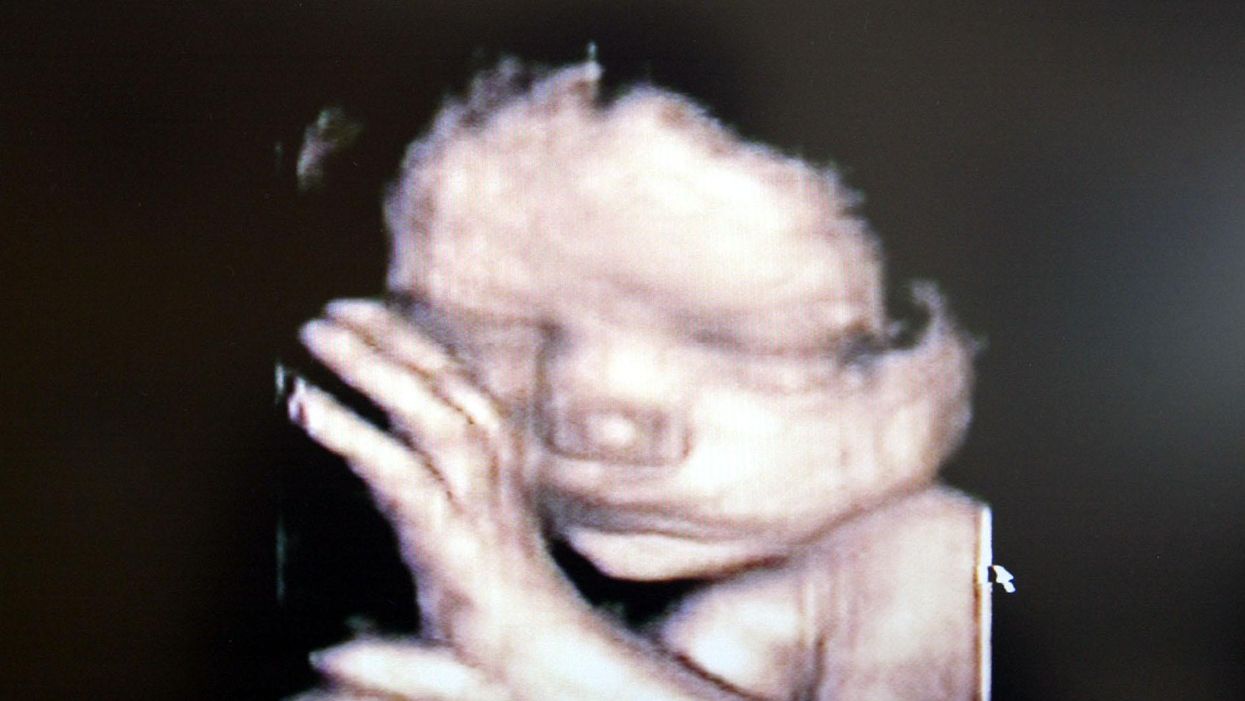

Photo by Fotopress/Getty Images